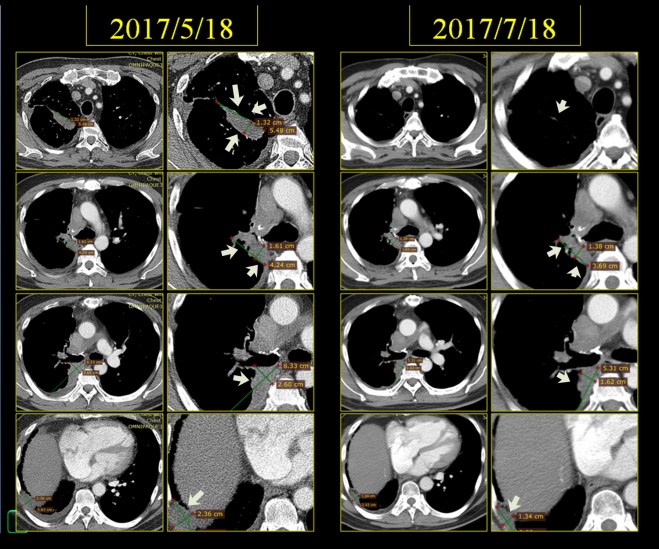

본원 내원 이후 보호자들의 근심스러운 얼굴에도 불구하고 환자의 상태는 좋아져서 chest와 CT 상의 변화를 보이게 되었다. 2017년 5월 18일 아산병원에서 가져온 CT를 본원에서 비교하였다. 환자 보호자는 주치의 선생이 달라진 게 없다고 하였다는 한마디를 하며 줄었다는 나의 이야기를 미심쩍어 하였다.

그리고 환자 분은 2017년 7월 18일 다시금 아산에서 CT를 촬영하여서 내게 방문을 하였고 역시 지속적으로 한약과 UFT를 더하자 더욱 많이 종양이 줄어든 것을 알 수가 있었다.

이 환자의 종양은 윗부분은 확연히 사라지고 가장 크기가 넓은 데가 1.6×4.2cm에서 1.38×3.69cm 로 다소 줄어들어 보인다. 체적으로 대비하면 꽤 줄었다고 볼 수 있다. 환자 보호자는 여전히 줄었어도 근심하는 얼굴이다. 최근에 황달수치가 1.2 기준에서 t-bil이 1.5로 상승하였기 때문에 한약 때문인가 걱정을 하였다. 나는 절대로 그럴 일은 없다고 이야기하였다. 체질에 안 맞으면 모를까 체질에 맞는 약은 오히려 간기능을 좋게 한다. 그래서 되물었다. 최근에 무언가 새로운것을 먹는것이 없냐고 물었더니 내게 고지하지 않고 이웃에서 권유한 효모를 먹고 있었다. 효모는 소양인 약으로 anti cholinergic 한 효과가 있다. 소음인에게서는 담즙배설을 억제시키고 담관의 괄약근을 수축시킨다. 아마도 이 때문이라고 생각되어서 환자에게 이를 중지시켰다. 다음 번에 효모를 끊고 나서 다시 혈액검사를 해 보면 알 일이다. 일반인들은 이를 따지는 기전을 모르기 때문에 급한 대로 누가 효과를 보았다면 먹고 싶어하지만 암환자는 사소한 약물, 식품 하나라도 영향을 받는다. 그래서 거듭 환자에게 음식주의와 운동을 할 것을 당부하였다.

다음은 이 환자의 초기 2017년 4월 3일 CT와 이후 내원하여 4월 17일부터 한약 복용하고 한 달 뒤인 5월 18일 사진, 그리고 치료 3달 뒤인 7월 18일 사진을 coronal view (세운 채로 쪼갠 사진으로 앞에서 뒤로 단면이 cut된 사진)를 제시해 보면 확연히 종양이 줄어드는 것을 알 수가 있다. 그리고 또한 pleural thickening도 많이 감소된 것을 보게 된다. 비록 아산 소견서는 별 변화 없는것처럼 들었다고 하였지만 이 같은 차이가 쉽게 얻어지는 것은 아니며, 한약 양약 환자와 보호자의 노력이 합쳐져서 얻어지는 것임을 명심해야 한다.

다음 cut에서 확연히 우측 늑막의 pleural thickening이 줄어든 것을 볼 수 있다.

이 환자의 종양은 명확히 범주를 정하기에는 불규칙한 모양을 하고 있으나 대략 가장 크게 보이는 데를 기준으로 하여서 체적을 측정하면 (이는 전문가가 아닌 나의 측정이므로 오차가 꽤 있을 수는 있음을 양해를 구한다) 4월 3일 52CC 정도에서 한 달 치료 후에 35CC 정도로 감소되었고 또 7월 18일 마지막에는 18CC 정도로 줄었다고 볼 수 있다.